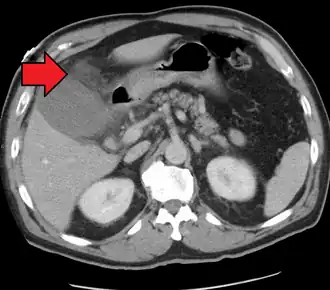

![]() Colecistitis aguda como se ve en la TC. Obsérvese la acumulación de grasa alrededor de la vesícula biliar agrandada. | ||